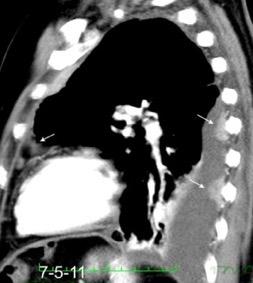

Signo de la Pleura separada “Split pleural sign”

Capas pleurales de grosor uniforme realzadas por el contraste

No específico de empiema. Indica “exudado”. 68% de pacientes con empiema pleural.

Capas pleurales de grosor uniforme

Realce grasa extrapleural (30%)

> Grasa Extrapleural. (60-80%)

Kraus GJ. Split pleural sign. Radiology 2007